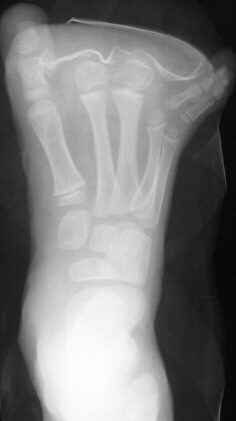

of right foot, at age 5 years, she underwent partial amputation of the

right 2nd and 3rd metatarsals(images 3 & 4). Now at age 10, she has

been doing well, participating in all sports. She has noted that there

has been some difficulty in finding shoes that fits but does not complain

of any pain.